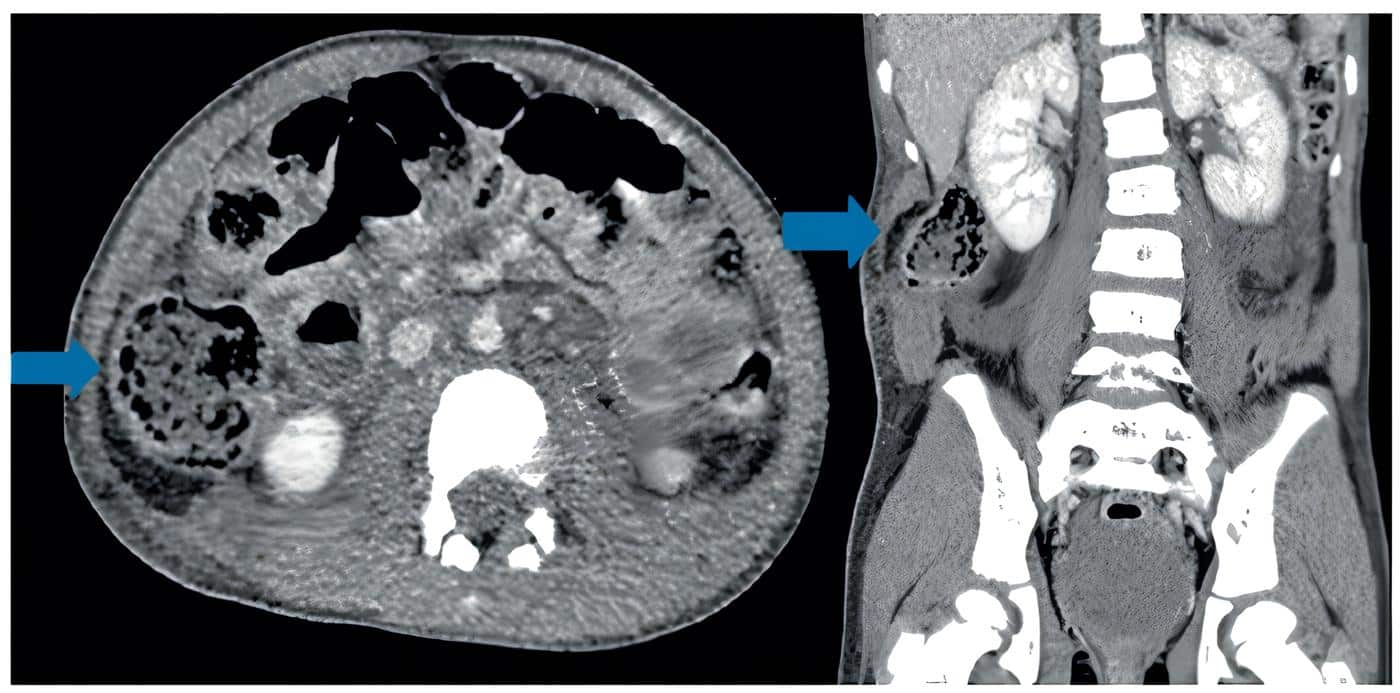

Se practicó TC abdominal (Figura 4) que diagnosticó hernia traumática de la pared abdominal, por lo que se programó para cirugía.

Figura 4. Hernias traumáticas de la pared abdominal en corte axial y corte coronal. Note la

herniación visceral en el flanco derecho. Las flechas muestran la hernia traumática.

Fuente: servicio de radiología del hospital Pablo Tobón Uribe, Medellín, Colombia.

En el procedimiento quirúrgico se encontró ruptura de la fascia y de los músculos recto abdominal, oblicuos interno, transverso y oblicuo externo, conformando un defecto de 6 cm de longitud, con contenido herniario de colon ascendente y despulimiento de su serosa, sin perforación de asas ni otras lesiones asociadas.